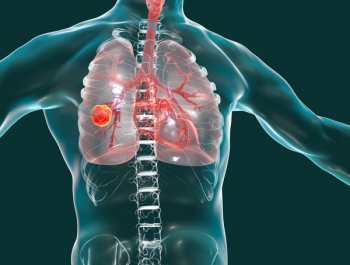

Investigators reported that, compared with chemotherapy, atezolizumab monotherapy was superior in overall survival and progression-free survival in patients with NSCLC.